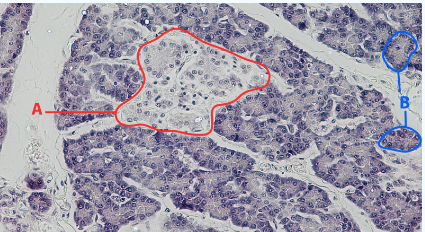

A

Islet

B

Acinar cells

Area

Pancreas